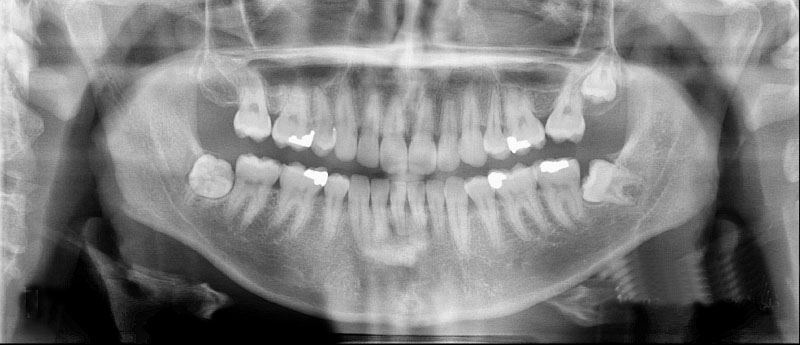

Oral Diagnoz ve Radyoloji